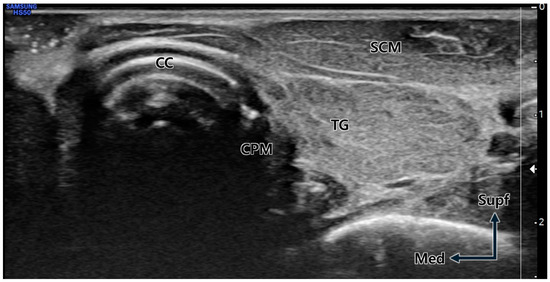

The initial step for precise US-guided BNT injection into the CPM is identifying the CPM within the US view [21]. Since the left lateral areas of the CPM attached to the cricoid cartilage are superficially located close to the US probe, this area was relatively well visualized in this study. Therefore, the lateral areas of the CPM have become the optimal target point for BNT injection when using the US-guided technique. However, the CPM attached to the right side of the cricoid cartilage is not well visualized compared to that on the left side [11,21,22]. This point is thought to account for the injection failure rate being somewhat high on the right side, even though there was no statistical difference in success rate between both sides. Therefore, the cricoid cartilage is the most important landmark for advancing the injection needle into the CPM, especially in the right-side procedure. In the present study, the cricoid cartilage was used as a reliable landmark for US-guided injections to locate the CPM [8,9]. We recommend scanning the longitudinal and transverse planes to identify detailed anatomical structures surrounding the larynx, including the CPM, prior to localization. The first step is to identify the cricoid cartilage by palpation, followed by scanning the neck in the longitudinal plane to establish the transverse position of the US probe. When positioning the US probe transversely, the sternocleidomastoid muscle, thyroid gland, inferior border of the cricoid cartilage, common carotid artery, and the surface of the vertebral body served as useful landmarks to identify the CPM before injection [21]. After localizing the CPM via the US, we recommend advancing the needle along the surface of the cricoid cartilage, considering its proximal relationship with the CPM [8,9]. Utmost care should be taken during needle insertion to ensure that the thyroid gland and common carotid artery are not damaged along the needle’s path and that the needle tip does not project beyond the CPM, potentially reaching the prevertebral space and fascia (e.g., the surface of the vertebral body). As the needle is not advanced once it reaches the prevertebral fascia, it should be pulled back in order to find the needle tip in this situation.

5.3. US Scanning Protocol

Utilizing the HS50 device (Samsung, Seoul, Republic of Korea) coupled with a linear array transducer (LA3-14AD, 3–14 MHz), we performed real-time B-mode US scanning. Before scanning, the head of the cadaver was rotated as far as possible to the opposite side to ensure that the skin of the laryngeal area and the US transducer were perpendicular, facilitating easy US imaging. Then, the anterior side of the neck was palpated to identify and mark the cricoid cartilage, which is a key anatomical landmark of the larynx.

The neck of the cadavers was extended as much as possible to facilitate application of the probe at an approximately 90° angle to the skin. By palpating the anterior side of the neck, we identified the thyroid and cricoid cartilages, which are key anatomical landmarks for applying various transcutaneous procedures into the larynx. The superior and inferior boundaries of the cricoid cartilage were marked at the skin. The transducer was aligned transversely to conduct scans across the inferior boundary of the cricoid cartilage guided by demarcations and anatomical features. When the transducer was tilted slightly upward at the lower boundary of the cricoid cartilage, strap muscles, cricoid cartilage, thyroid gland, and carotid artery could be observed simultaneously on US.

The US-guided injection procedures were conducted using a 6 cm long 24G needle, with the target depth preliminarily determined through US imaging. For observation of the cricoid cartilage, CPM, and common carotid artery, the transducer was placed on the lateral border of the cricoid cartilage using the out-of-plane method (Figure 5).

Figure 5. Transverse ultrasound image at the cricoid cartilage (CC) level. Due to the neck rotation to the lateral side, the cricopharyngeus muscle (CPM) is prominently visible immediately lateral (posterior) to the distinctly observed CC. TG; thyroid gland, SCM; sternocleidomastoid muscle, Supf; superficial, Med; medial.